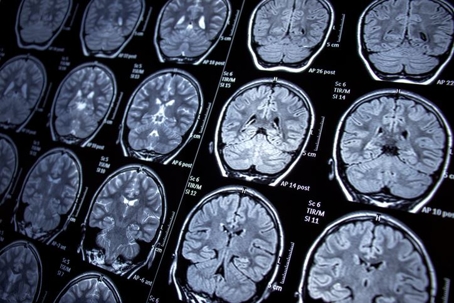

MRI

4. Traumatic Brain Injuries (TBIs): TBIs can vary in severity from concussions to brain damage. These injuries may occur due to head trauma, like during a car crash, or oxygen deprivation, such as in drowning incidents. TBIs can lead to motor control loss, paralysis, personality changes, or cognitive impairments. The long-term effects of TBIs may not be immediately apparent, making them unpredictable and challenging to deal with.